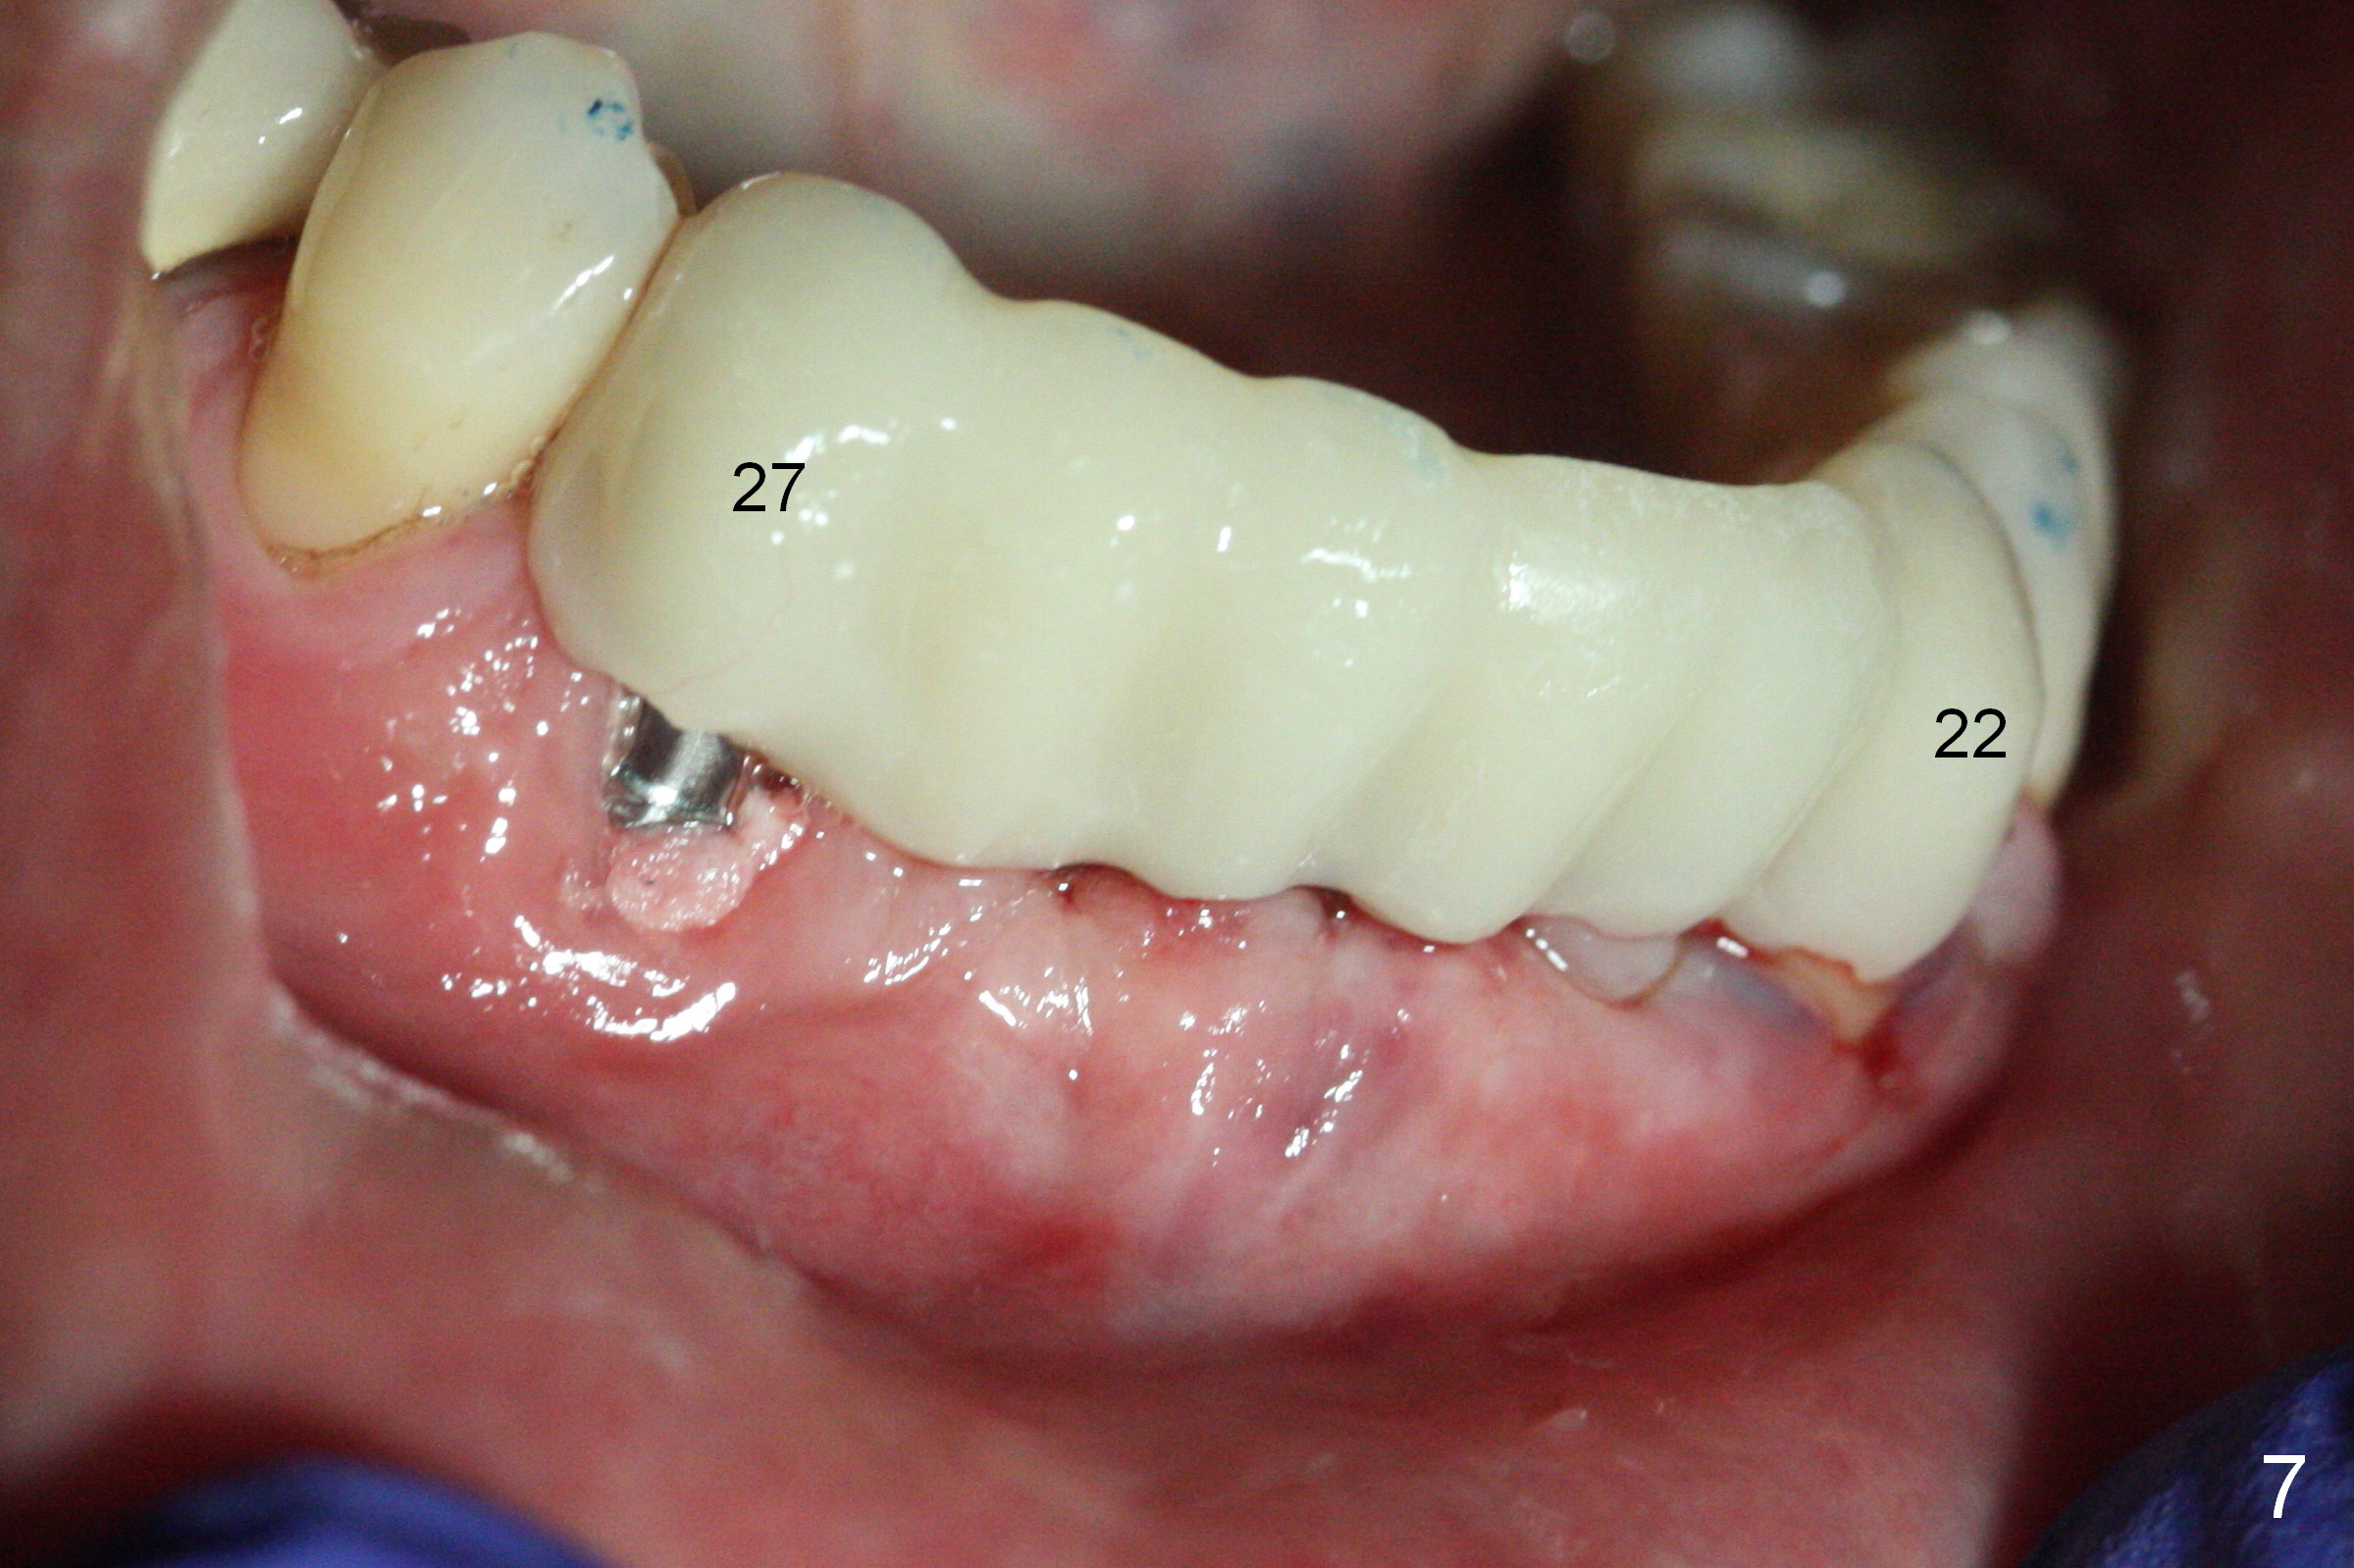

There is severe buccal gingival recession at #27 (Fig.1 arrow), as compared to that at #22. After removing the bridge and extraction of #27 (Fig.2 with severe loss of the buccal plate), a 3x18 mm drill is used to finish osteotomy (Fig.3). A 3.8x13 mm UF implant (Fig.3 green line) will be placed with 9 mm in the apparently solid, native (new) bone (blue line), while the coronal 5 mm will be occupied by the 5 mm cuff of a cemented abutment (pink line). The white dashed line is the gingival margin. The osteotomy is initiated as lingual as possible so that there will be at least 2 mm buccal gap when the narrow implant is placed. In spite of effort and precaution (guided surgery could control the trajetory), the coronal end of the implant tilts buccally so that a 4.5 mm 15 ° A 4 mm angled abutment is placed slightly subgingival (except buccal; Fig.5 A).

Since the ridge between the lower canines is atrophic (Fig.2), osteotomy starts at #23 and 25 after crestal reduction (Fig.4 arrowheads), Two of 2.5x12(4) mm 1-piece implants are placed (Fig.6). The implants at #23, 25 and 27 and the tooth #22 support an immediate provisional bridge (Fig.7).

The mesial defect at #27 appears to have been repaired 8 months postop (Fig.8,9 *); there is no bone loss at 1-piece implant sites. The gingival recession seems to remain the same before and after removal of the provisional FPD (Fig.10,11). The bulging abutment at the cervix is less prominent when a straight abutment is used and prepared (Fig.12, 4.5x5.5(5) mm). There is no bone loss at #23, 25 and 27 sites 2.5 years post cementation (Fig.12-15), although the trajectory of the implants could be improved by using surgical guide (Fig.16-18).